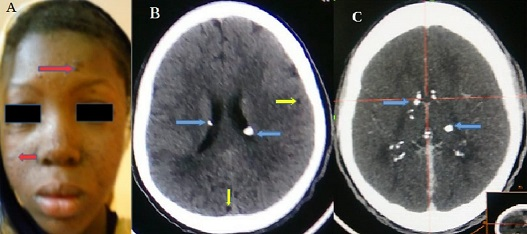

Tuberous sclerosis complex (TSC) is a multisystem genetic disease. Its incidence is estimated from 1/5800 to 1/1000 births. It results from the mutation of the TSC1 gene on chromosome 9 which codes for hamartin or the mutation of the TSC2 gene on chromosome 16 which codes for tuberin. In 80% of cases, it is linked to a neo-mutation and in 20% of cases it is autosomal dominant inherited from one of the parents. It is a multisystemic disease characterized by the presence of dysplasias, hamartomas and neoplasias in various organs: skin, kidneys, eyes, heart, lungs and mainly the brain. Clinically, epilepsy is the major complication of TSC and approximately 80-90% of patients will develop epilepsy in their lifetime. These epilepsies aren't specific but are generally characterized during evolution by their phamaco-resistance or by the complexity of the seizures. We report the case of a 12-year-old woman with partial epilepsy secondarily generalized, mental retardation and progressive facial angiofibromas (A) for 7 years. The electroencephalogram (EEG) performed 1 year ago showed bihemispheric irritant signs predominant at the frontotemporal right. The brain CT Scan with (B) and without injection of iodinated contrast agent (C) shows calcified subependymal nodules with supratentorial seat with bilateral asymmetric involvement and uncalcified cortical tubercles. The addition of the characteristic triad (convulsion, mental retardation and sebaceous adenoma) to the CT data enabled us to conclude a TSC. The evolution of convulsive seizures was significantly favorable under antiepileptic monotherapy (phenobarbital). On the other hand, mental retardation persists and angiofibromas continue to multiply at the facial level.